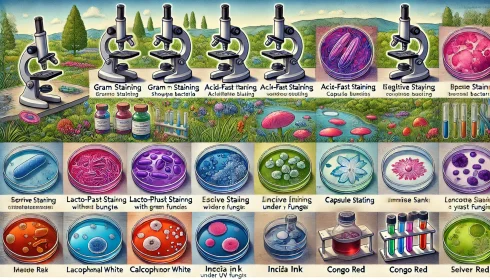

انواع رنگآمیزی مورد استفاده در میکروبیولوژی

مقدمهای بر انواع رنگآمیزی مورد استفاده در میکروبیولوژی انواع مختلفی از رنگآمیزی وجود دارد که[بیشتر بخوانید]

4 دیدگاه